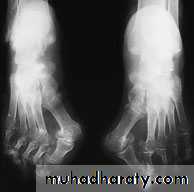

Rheumatoid arthritis of the ankle and foot:

The foot is affected as common as the hand and the disease pass in its three stages,

1st. stage of synovitis that affects ankle, intertarsal and other small joints, also affects synovial tendon sheath of different tendons mainly the tibialis posterior and the peronei.2nd.stage of erosion of the articular cartilage and tendons that can be torn.

3rd. stage of severe deformity and dysfunction with the characteristic deformities of foot valgus, forefoot splaying, hallux valgus and toe clawing.

There will be lot of planter callosities and dorsal corns that may get inflamed or infected and sometimes ulcerate.

Patient having progressive pain and discomfort with difficulties in shoe wear and walking. There is limitation of movements and gradual development of deformities, callosities and corns.X-ray: May show the joint erosions and foot deformities.